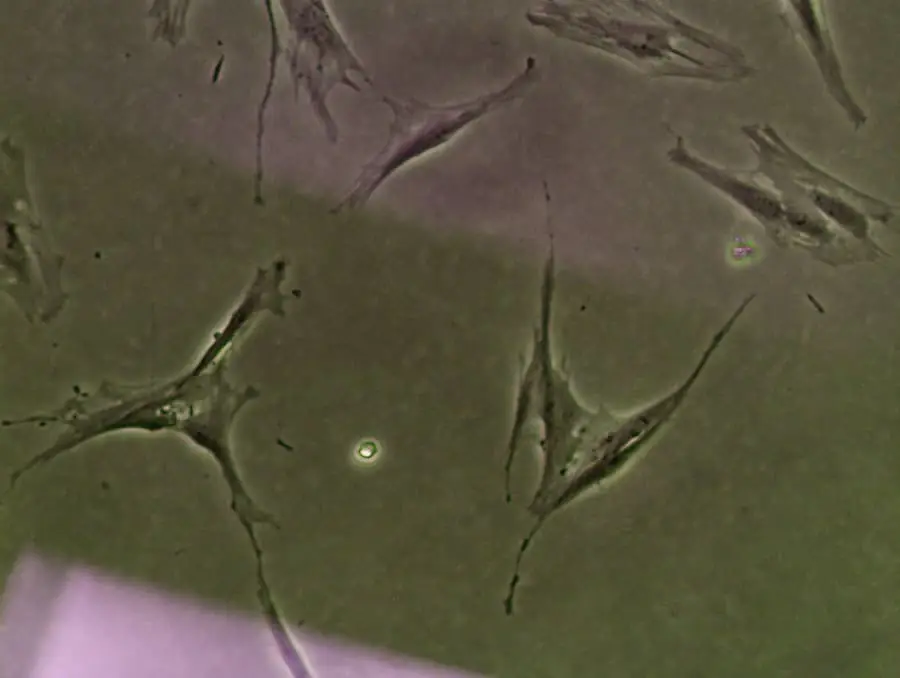

在用于治療患者之前,我們會(huì)多次徹底檢查每種干細(xì)胞產(chǎn)品。借助我們的內(nèi)部實(shí)驗(yàn)室,我們可以密切監(jiān)測(cè)干細(xì)胞的成分和活力,確保劑量安全有效。

使用顯微鏡監(jiān)測(cè)干細(xì)胞的活力